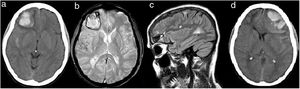

(a) CT brain (2014) showing right frontal hemorrhage and subarachnoid hemorrhage around temporal lobe. (b) Gradient Echo T2 sequence one month later showing hypointense signal around temporal lobe due to subarachnoid hemorrhage and around right frontal hemorrhage. No hypointense signals suggestive of microbleeds are showed. (c) High signal lesions on axial FLAIR-T2 sequence one month later showing juxtacortical and periventricular lesions suggestive of MS diagnosis. (d) CT brain (2019) showing left frontal hemorrhage, subarachnoid hemorrhage around frontal and temporal lobe, and mass effect.

Initial blood pressure was 127/72mmHg. Routine laboratory tests and drugs in urine were normal on admission. An extensive coagulopathy panel, including platelet count and function tests, coagulation times, and hemorrhagic diathesis was uninformative. Serologies were also negative. A cerebral angiography did not find any aneurysm, arterial or venous malformations. A brain MRI did not show any underlying vascular abnormality, signs of vasculitis, brain tumor or cerebral microbleeds one month later (Fig. 1b and c). Brain biopsy was not performed. The patient did not have any personal or familial history of spontaneous bleeding, nor during minor surgeries. She did not have history of cognitive impairment or other vascular risk factors apart from smoking. The patient recovered appropriately and no neurosurgical treatment was needed.